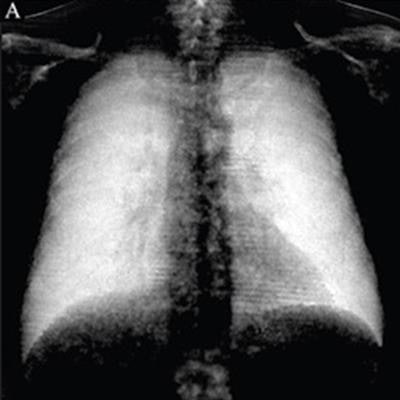

Digital X-Ray Special FeatureSep 18, 2019 Dark-field chest x-ray measures up to CT for diagnosing emphysema Latest in HomeTheranostic pair ready for testing in lung cancerJanuary 8, 20262025's budget bill could lead to more than 1M missed cancer screeningsJanuary 8, 2026LLMs in radiology may find opening in updated FDA guidanceJanuary 8, 2026Diffusion motion correction boosts portable brain CT image qualityJanuary 7, 2026Related StoriesHomeYouth movement sweeps radiology in 2018 Minnies awardsHomeYouth movement sweeps radiology in 2018 Minnies awardsHomeMeet the Minnies 2018 finalistsHomeMeet the Minnies 2018 finalists